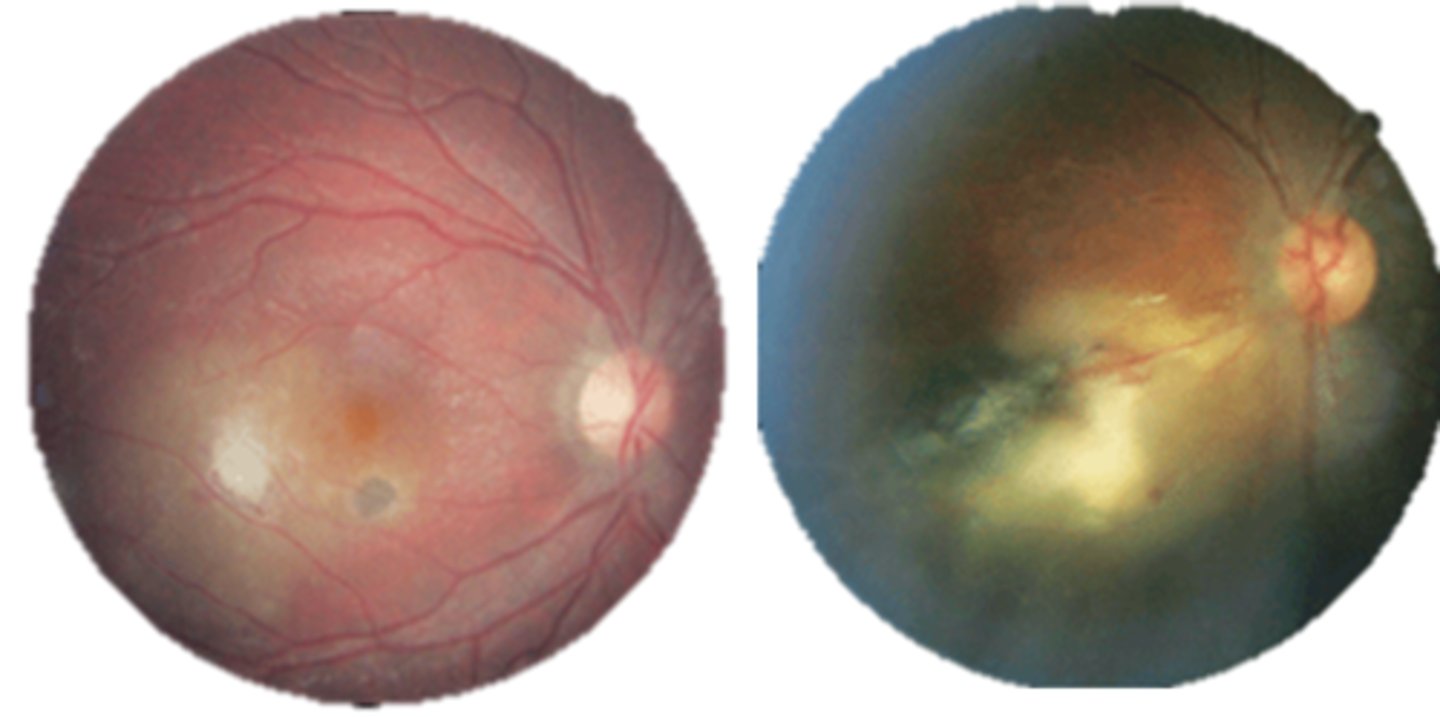

What finding of toxoplasmosis is seen in A/B?

retinitis turns into hazy scar with nerve pallor

What finding of toxoplasmosis is seen in C/D?

scarring overtime with VA loss/scotoma